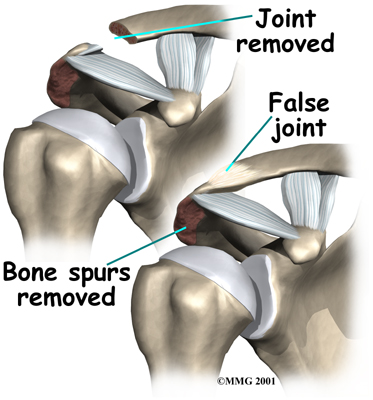

Resection Arthroplasty

Impingement may not be the only problem in an aging or overused shoulder. It is very common to also see degeneration from arthritis in the AC joint. If there is reason to believe that the AC joint is arthritic, the end of the clavicle may be removed during impingement surgery. This procedure is called a resection arthroplasty.

The most common procedure for AC joint osteoarthritis is resection arthroplasty. A resection arthroplasty involves removing a small portion of the end of the clavicle. This leaves a space between the acromion (the piece of the scapula that meets your shoulder) and the cut end of the clavicle, where the joint used to be. Your surgeon will take care not to remove too much of the end of the clavicle to prevent any damage to the ligaments holding the joint together. Usually only a small portion is removed, less than one cm (about three-eighths of an inch). As your body heals, the joint is replaced by scar tissue. Remember, the AC joint doesn't move much, but it does need to be flexible. The scar tissue allows movement but stops the bone ends from rubbing together.

This procedure can be done in two ways. Today, it is more common to do this procedure using the arthroscope. An arthroscope is a slender tool with a tiny TV camera on the end. It lets the surgeon work in the joint through a very small incision. This may result in less damage to the normal tissues surrounding the joint, leading to faster healing and recovery.